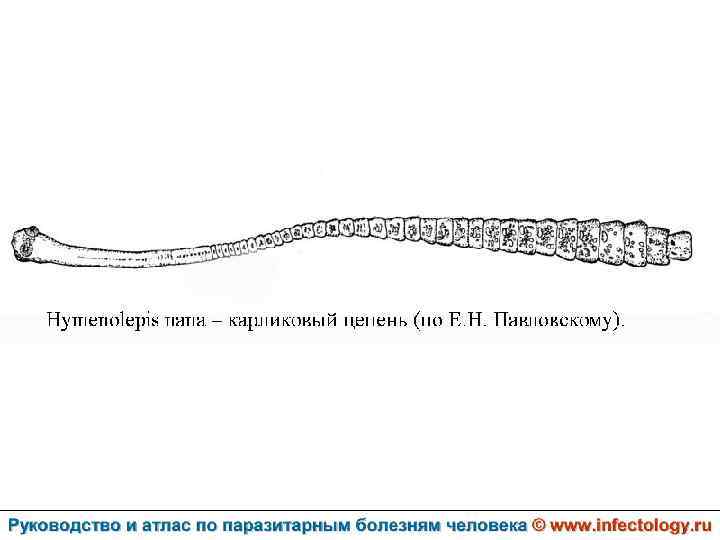

Гименолепидоз (шифр по МКБ 10 – B 71. 0) – контагиозный гельминтоз человека и некоторых мышевидных грызунов, характеризующийся, главным образом, нарушениями функций пищеварительного тракта.